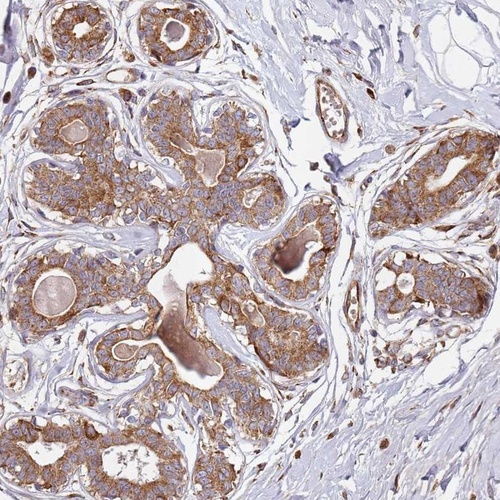

Immunohistochemical staining of human breast shows moderate cytoplasmic positivity in glandular cells.